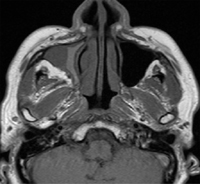

MRI

右上顎洞の炎症所見

積極的に腫瘍性病変を示す所見なし

高タンパク内容を反映する信号強度

MRIT2強調冠状断像

MRIT1強調横断像

MRIT2強調横断像